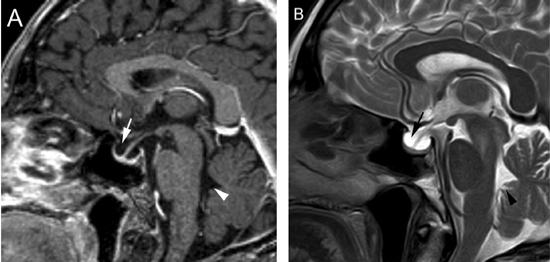

También con la mayor edad se produce involución de la glándula22, lo que puede acentuarse con el desarrollo de una hernia de la cisterna supraselar en la fosa pituitaria, que en grados avanzados constituye un aracnoidocele selar. En estos casos la silla turca puede estar aumentada de tamaño sin que exista un tumor; esto se debe a las pulsaciones del líquido cefalorraquideo(LCR) transmitidos a través de la apertura normal del diafragma selar, que en un 20% de la población puede estar ausente o presentar una dehiscencia adquirida, lo que inicialmente fue descrito en patología como "silla turca vacía"23. Esta situación de vacuidad no es tal, porque en realidad la silla turca está ocupada por líquido cefalorraquideo y una glándula pituitaria aplanada, con un tallo pituitario elongado (Figuras 9A y 9B), condición que se observa con mayor frecuencia en mujeres sobre los 50 años, obesas y multíparas. Se ha descrito en un 5,5 % de las autopsias y generalmente se trata de una condición primaria, habitualmente asintomática. En los casos secundarios, cuando hay causas como la cirugía o radioterapia, puede asociarse con alteraciones del campo visual por adherencias que deforman el quiasma óptico24.

Figura 9A y B. Cortes sagitales, secuencias T1wl con Gadolinio y T2w, muestran la hipófisis en la porción inferior de la fosa pituitaria, lo que es secundario a una herniación de la cisterna supraselar (flecha). Obsérvese que el tallo pituitario esta también descendido. La secuencia T2w permite confirmar que la señal del líquido en la fosa pituitaria es similar al LCR del IV ventrículo (punta de flecha). Tumores pituitarios